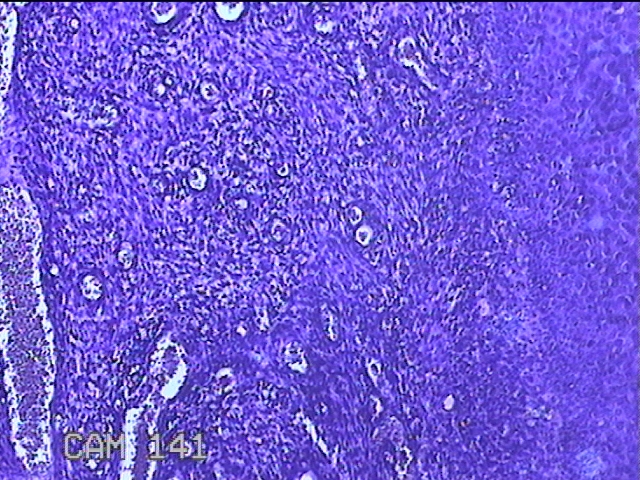

宫颈赘生物

性别

女

年龄

49岁

临床诊断

人乳头瘤病毒感染

一般病史

宫颈HPV阳性TCTLSLL

标本名称

大体所见

灰白粉红色肿物1.2x0.8x0.2cm两个,表面光滑。

图1